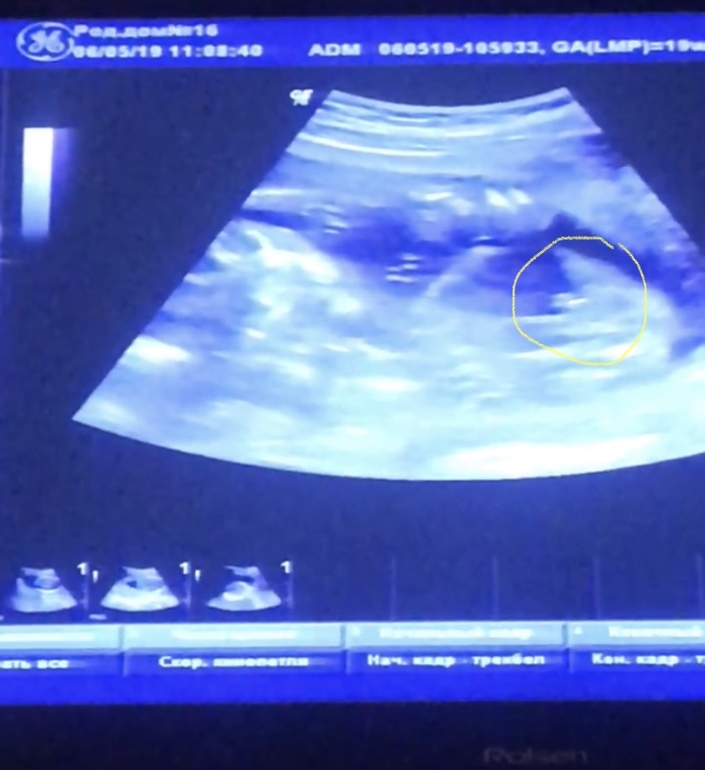

Сначала пообещали девочку, потом мальчика( фото прилагаю, но я думаю, что врач ошиблась), а сегодня малыш прятался и точно пол не сказали

Я, честно говоря, думала, что в Санкт-Петербурге такое вообще невозможно. Аппарат УЗИ хороший. Врач с опытом. Вот так и ошибаются с полом.

Да видно что аппарат хороший по снимку,я не так давно пост выкладывала там девушка выкладывала похожее фото и писала что по узи была девочка а родился мальчик вот так бывает..)